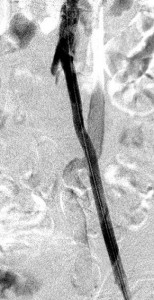

The images below illustrate percutaneous stenting of stenosis of the distal proximal and the mid left common iliac artery, without disease of the left external iliac artery in one of my patients who presented with left calf claudication. CTA of his abdominal aorta and arterial duplex ultrasound of his lower limbs ( images not shown) revealed left iliac stenosis, confirmed by the digital subtraction angiographic images in the first row. He did well following stenting of the diseased artery. Iliac arterial stenting stays open for nearly as long as surgical revascularization and at much less the morbidity and cost of the latter.